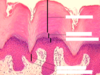

What are the 5 epidermis layers?

- Stratum Basale

- Stratum Spinosum

- Stratum Granulosum

- Stratum Lucidum

- Stratum Corneum

What stratum layer is letter A?

Stratum Corneum

What stratum layer is letter B?

Stratum Lucidum

What Stratum layer is letter D?

Stratum Spinosum

What Stratum Layer is letter E?

Stratum Basale

What Stratum Layer is letter C?

Stratum Granulosum